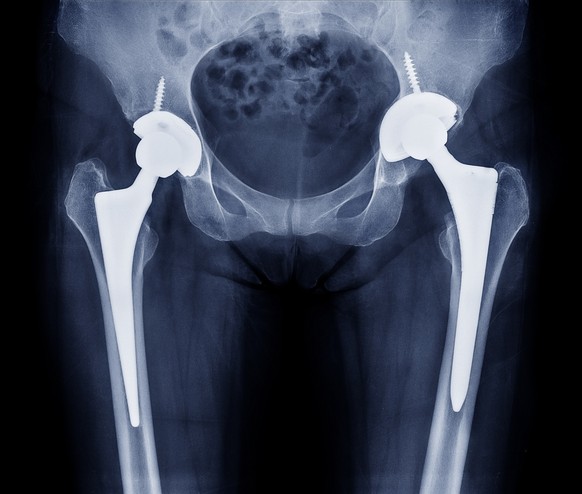

Allein in Deutschland seien im vergangenen Jahr 14'034 Mal Verletzungen, Todesfälle und andere Probleme im Zusammenhang mit Medizinprodukten wie künstlichen Hüft- oder Kniegelenken, Brustimplantaten oder Insulinpumpen gemeldet worden, berichteten am Sonntag die Sender NDR und WDR sowie die «Süddeutsche Zeitung».

Das Geschäft mit künstlichen Gelenken, Schrittmachern, Hörgeräten oder anderen Medizinprodukten sei laut Gesundheitsministerium mittlerweile auf einen Umfang von umgerechnet rund 300 Milliarden Franken weltweit gewachsen, heisst es in dem Bericht. Allein deutsche Unternehmen setzten etwa 30 Milliarden Euro mit diesen Produkten um.